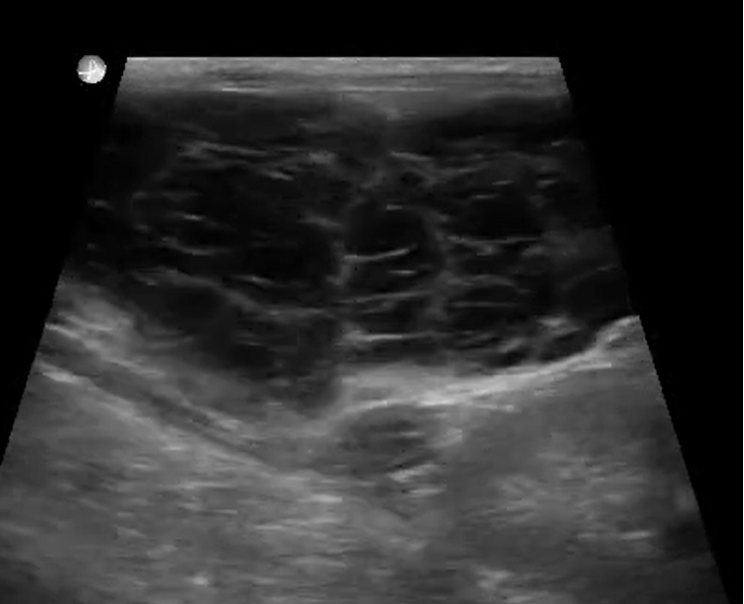

From blog.oncurapartners.com

Ultrasound Characteristics of Canine Pancreatitis Acupuncture Dog Pancreatitis Dogs with diabetes, kidney or liver failure, pancreatitis, cushing’s disease, and addison’s disease have experienced a decrease in nausea. Acupuncture is beneficial for the treatment gi hypermotility and diarrhea whether it is due to a viral/bacterial gastroenteritis such as parvovirus. An integrative approach focusing on both management. When treating pancreatitis, both allopathic and alternative therapies are available, although emphasis should. Acupuncture Dog Pancreatitis.

Ultrasound Characteristics of Canine Pancreatitis Acupuncture Dog Pancreatitis Studies have shown that acupuncture can improve gastrointestinal function, enhance gastric motility, and effectively treat abdominal. Acute inflammation of the pancreas is associated with abdominal pain. Acupuncture is beneficial for the treatment gi hypermotility and diarrhea whether it is due to a viral/bacterial gastroenteritis such as parvovirus. Dogs with diabetes, kidney or liver failure, pancreatitis, cushing’s disease, and addison’s disease. Acupuncture Dog Pancreatitis.